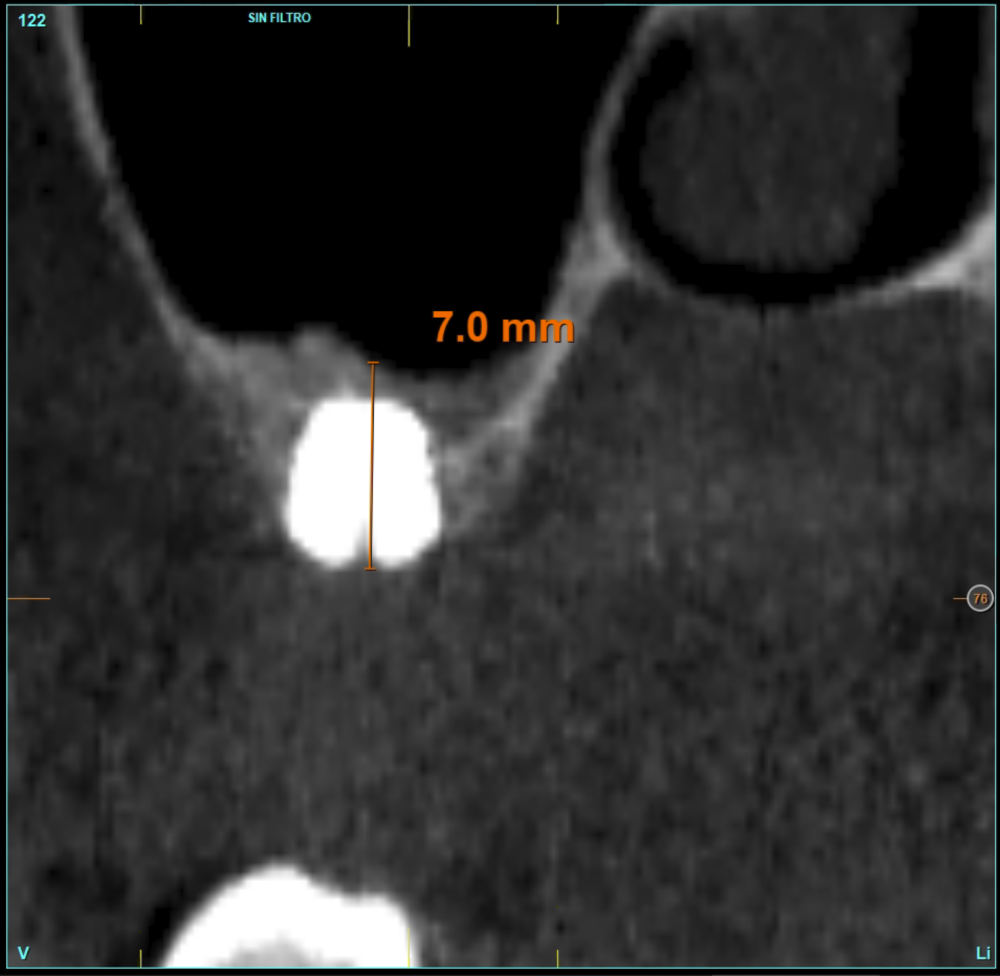

Material and method. A retrospective study has been carried out in patients in whom extra-short implants (4.5 and 5.5 mm length) were inserted directly by transcrestal elevation with residual ridges between 2 and 3 mm. The implant was the analysis unit for the descriptive statistics regarding location, implant dimensions, and radiographic measurements. The patient was the measurement unit for the analysis of age, sex and medical history. The main variable was the gain in height over the apex of the implant after 6 months of the surgery and one year after the load comparing both measurements and as secondary variables the biological complications and the implant failure were recorded.

Results. Ten patients who met the inclusion criteria were recruited and 20 implants were inserted. The mean residual bone volume height was 3.1 mm (+/- 0.3 mm with a range elevation above the apex of the implant in millimetres is of 2.8 mm (+/- 0.99 range 1.9 -5 mm). In the control cone-beam after one year of the studied load of the implants, the bone gain achieved was maintained, with no decrease in the volume gained, only three cases showed a decrease of between 0.4 and 0.5 mm of the initial volume at the end. No implants failed in the follow-up period and no biological complications were found in the surgery.